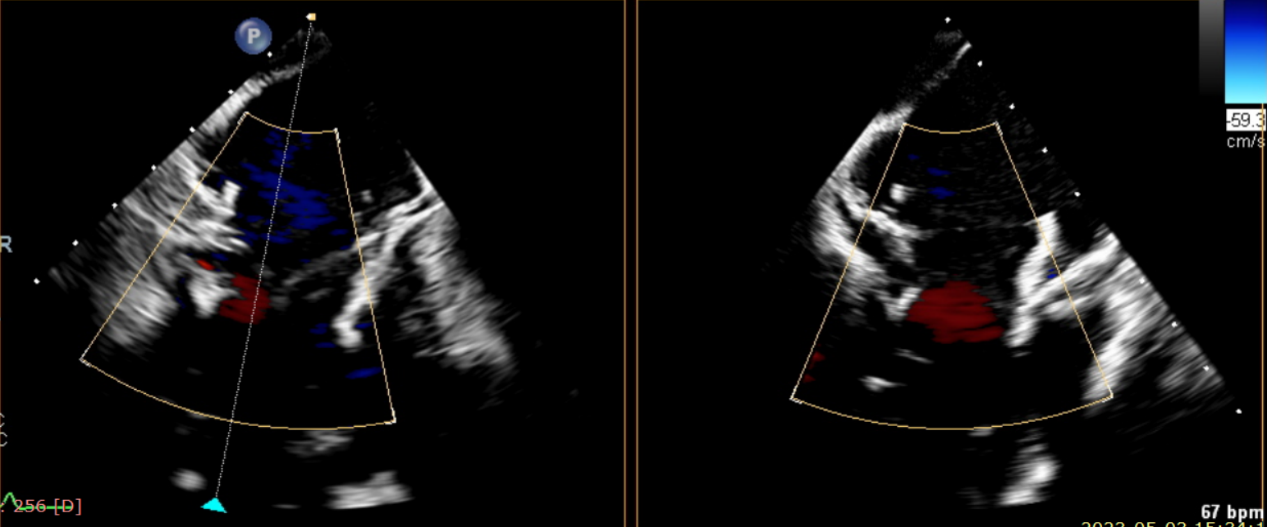

術后超聲提示無瓣周漏

術后超聲提示僅殘余輕微瓣周漏

術后Azeem Latib教授對LuX-Valve Plus經血管三尖瓣置換系統的器械性能和治療效果大為稱贊,并且認為LuX-Valve Plus的手術體驗非常好。從治療效果來看,術后即刻超聲顯示三尖瓣反流幾乎完全消失,血流動力學改善顯著,患者恢復快。在面對復雜解剖結構、超聲影像質量不佳、有起搏導線干擾時,Lux-Valve Plus也體現了極強的適應性。Thomas Modine教授參與了術中指導,他同樣再次肯定了LuX-Valve Plus術中操作的便捷性,認為LuX-Valve Plus容錯率高,對術中影像的依賴小,并表達了后期希望可以更多地應用LuX-Valve Plus三尖瓣置換系統于臨床實踐,讓更多的三尖瓣重度反流患者盡早獲益,改善預后。